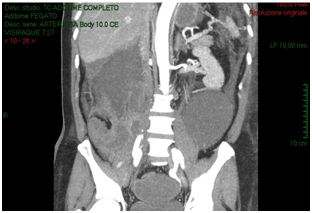

The CT-scan, targeted to a suspect of hemorrhage, did not have delayed phases. Patient received paracentesis with around 3200 cc fluid drained that was sent to microbiological examination. Result of bacteriological exam revealed infection by Proteus Mirabilis and he received target antibiotic therapy with resolution of septic status. In XXII post-operative day, for a progressive increase of serum creatinine we decided to perform an Uro-CT scan. The exam showed reduction of intraperitoneal fluid, right iliac side fluid collection with contrast enhancement during delayed phases; right ureter was not visible under fluid collection (Figure 3). We attempted to insert a ureteral stent in retrograde way but ureter resulted totally interrupted inside the fluid collection so the patient was undergone to explorative laparotomy and toilette of fluid collections. We found ureteral loss of substance of around 3 centimeter localized in anterior ureteral wall. We manufactured end-to-end ureteral anastomosis after positioning of ureteral stent seven French. We removed ureteral stent after 3 months and currently the patient is in follow-up with a good renal function as shown at last CT-scan after 10 months (Figure 4).

Figure 4: After ureteral stent removal, right ureter appears normal ducted with a good kidney function.